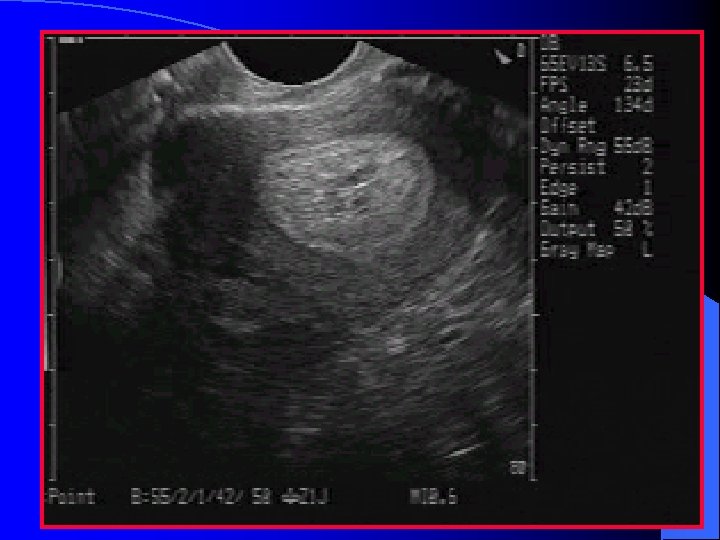

Ovaries l Lie posterior/lateral to the uterus l Anterior to the internal iliac vessels and medial to the external iliac vessels l Identified by a ring of follicles in the periphery

Ovaries After ovulation a corpus luteal cyst may be present – Observed in approximately 50% of ovulating females – Should not be seen beyond 72 hours into the next cycle l Small amount of fluid in the rectouterine pouch may be seen during ovulation l